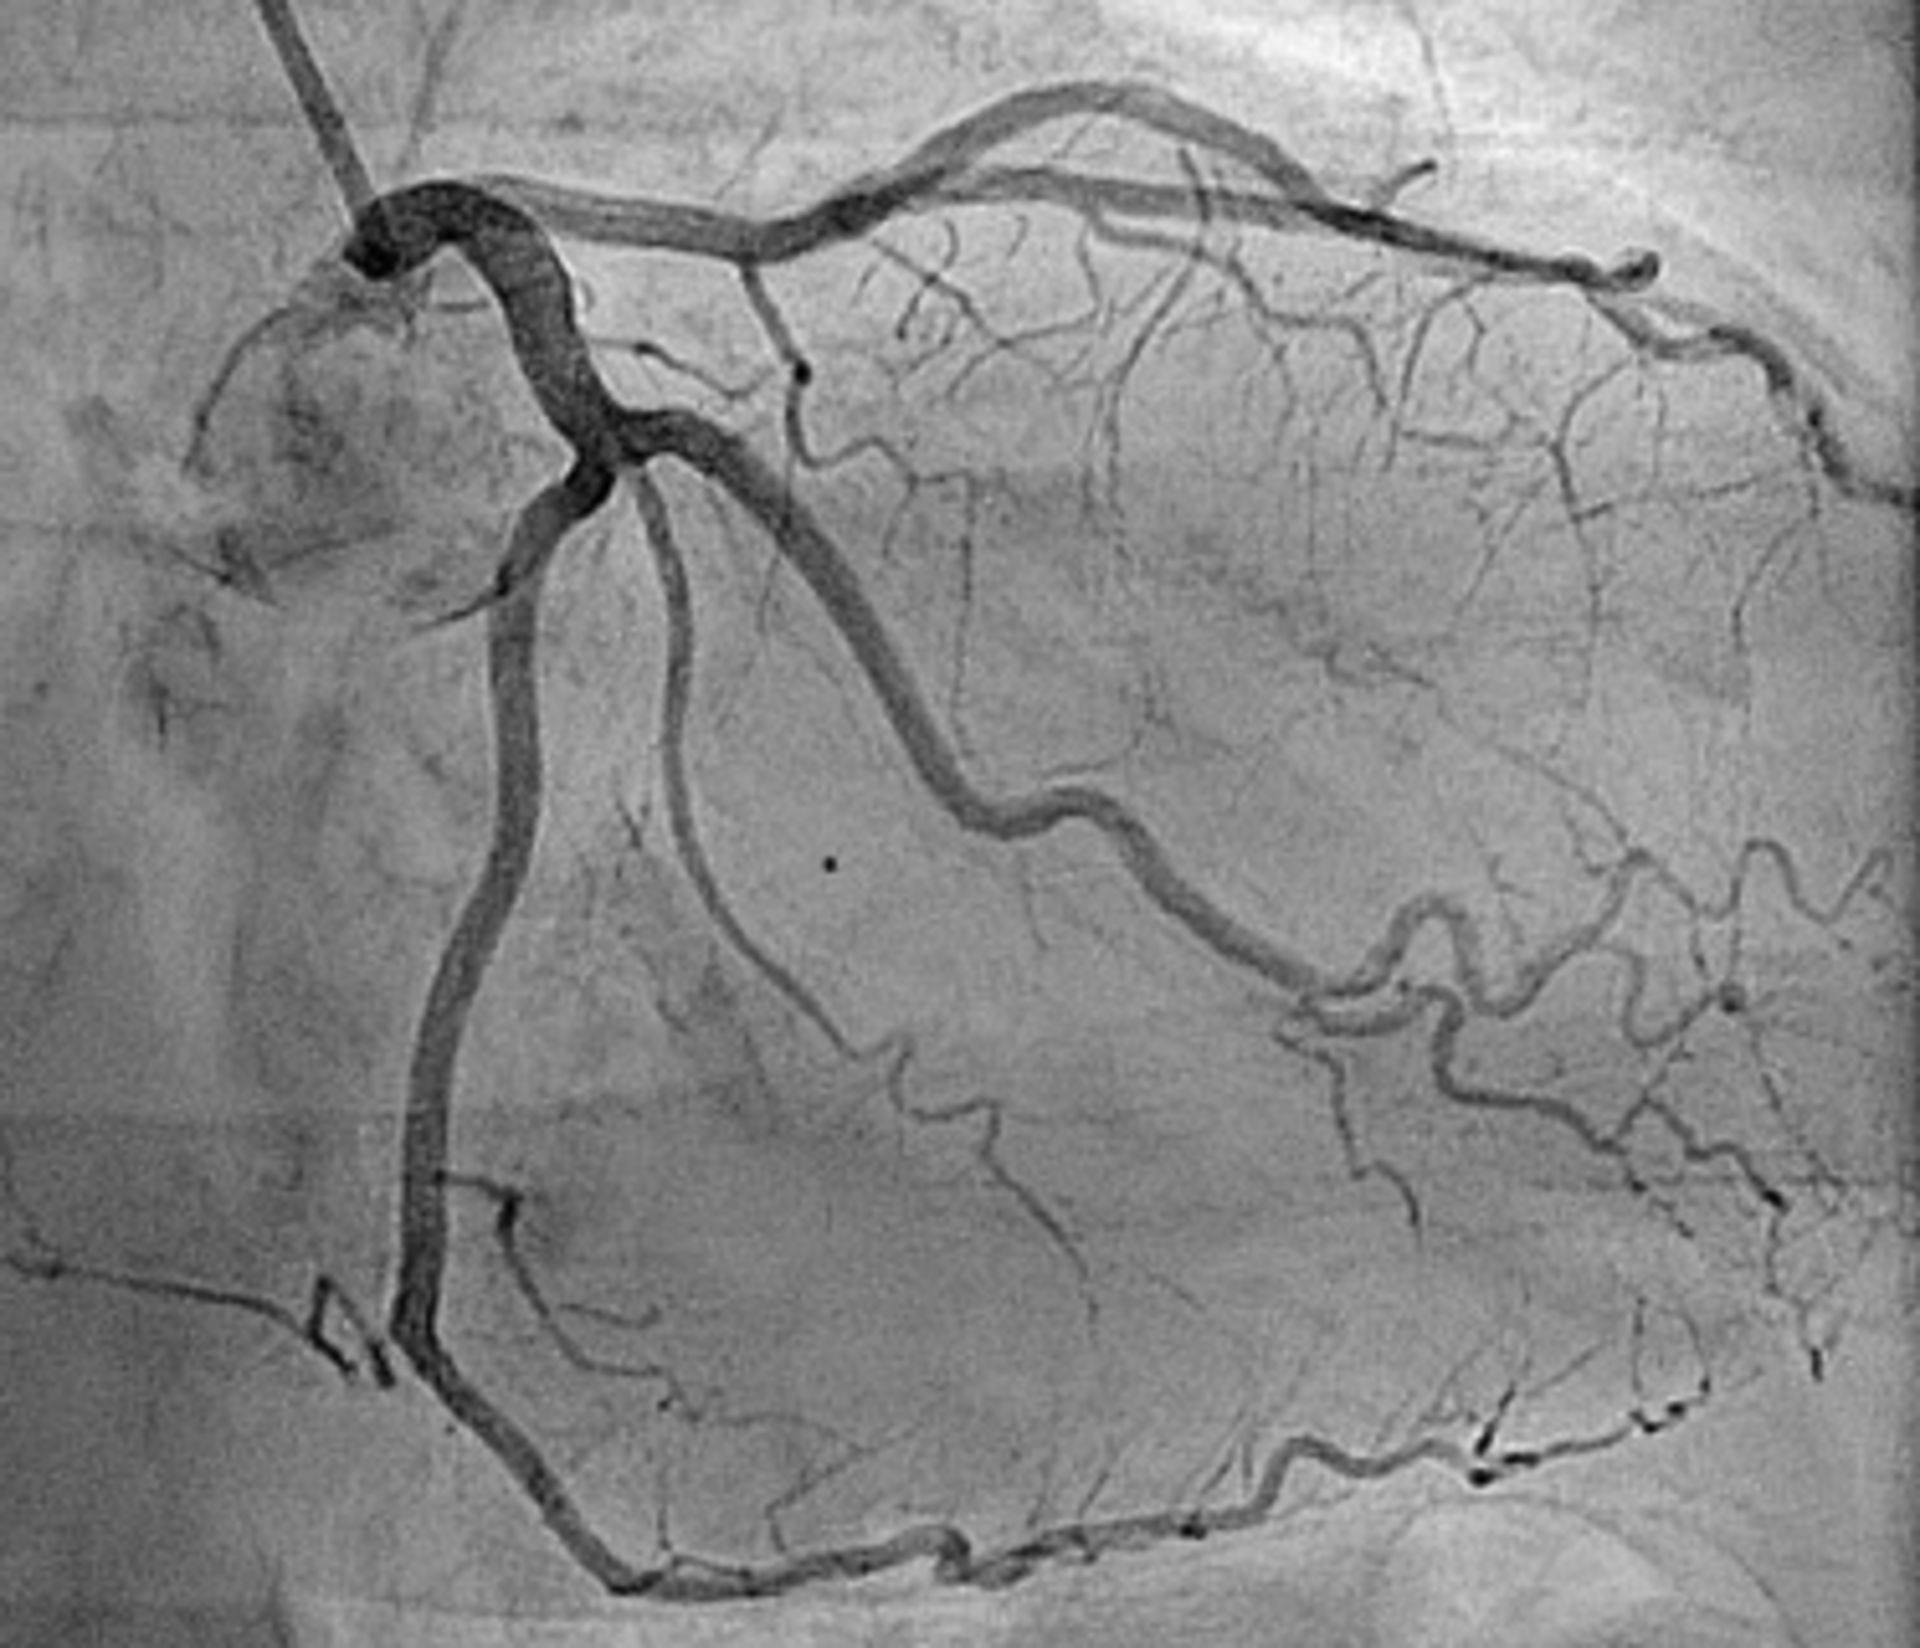

آنژیوگرافی روشی است که برای بررسی رگ‌های خونی استفاده می‌شود. در این روش، پزشک با تزریق رنگ مخصوصی به‌نام ماده‌ حاجب به خون بیمار، رگ‌های بیمار را با کمک نوعی اشعه‌ی ایکس بررسی می‌کند. تصاویر گرفته‌شده در این روش، بسیار کاربردی‌ هستند و به پزشک معالج کمک می‌کنند تا بتواند هرگونه گرفتگی را در رگ‌های بیمار تشخیص دهد.

تصاویر آنژیوگرافی که با نام «آنژیوگرام» شناخته می‌شوند، وضوح بسیار بالایی نسبت به نتایج عکس‌برداری معمولی دارند؛ بنابراین می‌توانند کمک بسیار بزرگی به پزشکان بکنند و اطلاعات لازم را برای شروع درمان مناسب در اختیار آن‌ها قرار دهند.

تصویر واضح عروق خونی در آنژیوگرافی

وضوح بالای عروق خونی در آنژیوگرافی